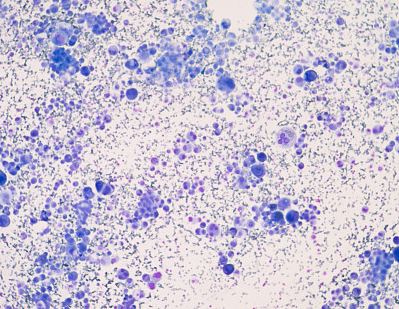

免疫细胞染色失败的几种原因

在深入探讨免疫细胞染色失败的几种原因时,我们不得不提及实验操作的细微差别对最终结果可能产生的深远影响。除了常见的抗体选择不当、样本处理失误外,还有几个容易被忽视但同样重要的因素值得探讨。

固定与通透步骤的精确控制至关重要。过度固定会导致细胞结构僵化,抗原表位被遮蔽,而固定不足则可能使细胞在后续步骤中易于破损,两者都会显著降低染色效果。同样,通透处理必须恰到好处,既要允许抗体充分渗透至细胞内目标区域,又要避免破坏细胞膜的完整性,从而保留住细胞内的宝贵信息。

(1)所染的全部切片均为阴性结果:包括阳性对照在内,全部呈阴性反应,原因可能是:①染色未严格按操作步骤进行;②漏加一种抗体,或抗体失效;③缓冲液内含*,抑制了酶的活性;④底物中所加H2O2量少或失效;⑤复染或脱水剂使用不当。

(2)所有切片均呈弱阳性反应:①切片在染色过程中抗体过浓,或干燥了;②缓冲液配制中未加氯化钠和pH值不准确,洗涤不*;③使用已变色的呈色底物溶液,或呈色反应时间过长;④抗体温育的时间过长;⑤H2O2浓度过高,呈色速度过快;⑥粘附剂太厚。

(3)所有切片背景过深;①未用酶消化处理切片;②切片或涂片过厚;③漂洗不够;④底物呈色反应过久;⑤蛋白质封闭不够或所用血清溶血;⑥使用全血清抗体稀释不够。

(4)阳性对照染色良好,检测的阳性标本呈阴性反应,固定和处理不当是zui常见的原因。

对于阳性结果的定量判断常规方法是根据呈色深浅和阳性细胞数量分类计数,以(-)、+、++、+++等分级和计数统计。现在已采用图象分析计量,本书第九章 将详细叙述这种使免疫细胞化学的定量成为可能的*的形态定量方法。另外,第十章 将详细途述另一种*的免疫细胞化学计量分类术-流式细胞光度计技术。